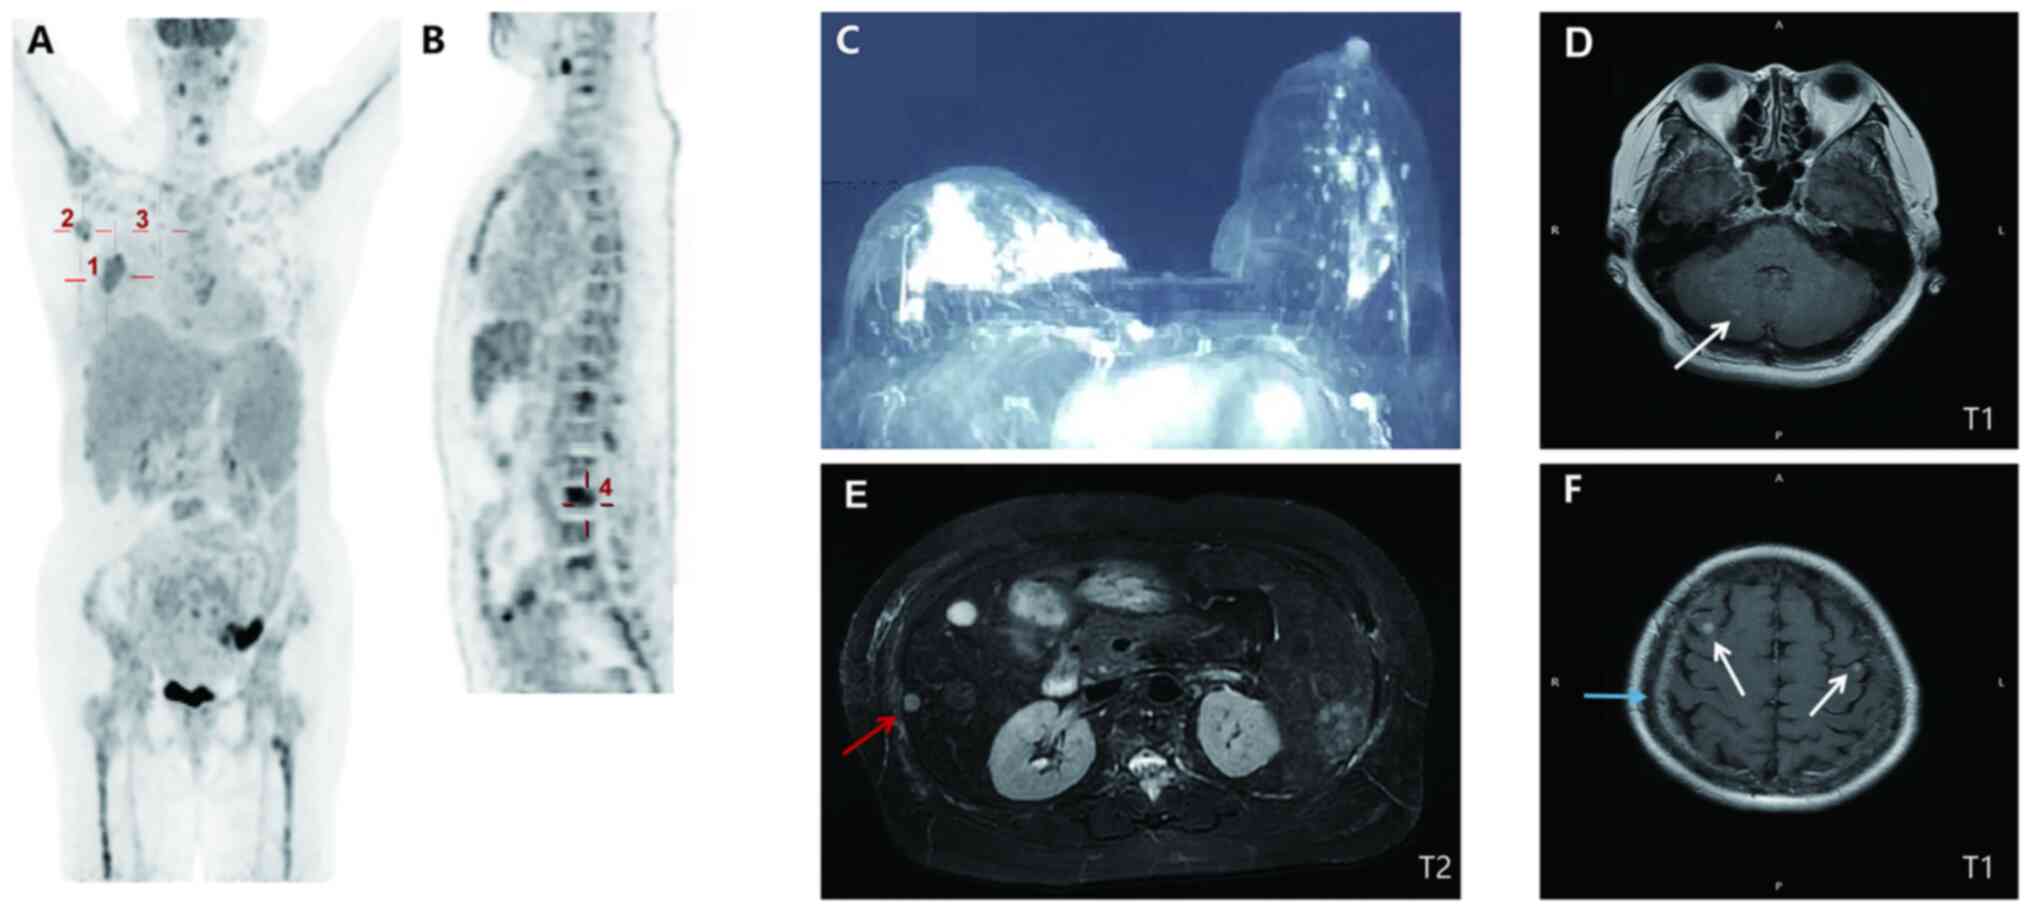

A 60-year-old postmenopausal female initially presented to Minhang Branch of Zhongshan Hospital, Fudan University (Shanghai, China) in April 2019 with a mass in the right breast, complaining of fatigue and lethargy. Physical examination revealed a 3.0-cm hard irregular mass in the central area of the right breast with inversion of the nipple and several swollen lymph nodes in the right axilla. Analysis of blood samples indicated markedly low hemoglobin level (48 g/l; normal range: 110–150 g/l) and platelet count (39×109/l; normal range: 100–300×109/l) with high levels of carcinoembryonic antigen (CEA; 203.70 ng/ml; normal range: 0–5 ng/ml), carbohydrate antigen 125 (CA125; 2,267 U/ml; normal range: 0–35 U/ml) and CA15-3 (4,754 U/ml; normal range: 0–25 U/ml). Contrast-enhanced breast magnetic resonance imaging (MRI) and computed tomography (CT) revealed right-sided breast malignant tumor with breast imaging-reporting and data system score of 5 (15) and the possibility of multiple axillary lymph nodes and multiple systemic bone metastases (Fig. 1). Pathology of the right breast performed based on the core needle biopsy indicated grade II invasive ductal carcinoma with the following immunohistochemistry (IHC) results: estrogen receptor (ER) (80%), progesterone receptor (PR) (−), HER2 (3+) and Ki-67 proliferation marker (Ki-67) (20%) (Fig. 2A). Furthermore, histology and IHC of bone marrow biopsy from the posterior superior iliac spine detected metastatic tumor cells (adenocarcinoma) with ER (+), PR (−), Ki-67 (<5%) and cytokeratin pan (CK-pan) (+) (Fig. 2B). Tissue samples derived from core needle and bone marrow biopsy specimens were fixed in 10% formalin at room temperature for 24 h, paraffin embedded and subjected to histological or immunohistochemical analysis. Sections (4 µm) were heated at 58°C for 2 h and then deparaffinized in xylene and hydrated with a series of graded alcohols, including anhydrous ethanol for 5 min, 95% ethanol for 2 min, 90% ethanol for 2 min, 80% ethanol for 2 min and 70% ethanol for 2 min. H&E staining was used for histological analysis. Antigen recovery was performed by heating and immersing the slides in citrate buffer (0.01 M, pH 9.0; cat. no., P0020; Beijing Noble Technology Co., Ltd.) in a microwave oven (121°C) for 10 min twice. Endogenous peroxidase activity was blocked using 3% hydrogen peroxide for 30 min at 20°C, and the sections were incubated with anti-ER (1:1 dilution; 37°C; 24 min; cat. no. 05278406001), anti-PR (1:1 dilution; 37°C; 24 min; cat. no. 05277990001), HER2 (1:1 dilution; 37°C; 20 min; cat. no. 05999570001; all from Roche Diagnostics), Ki-67 (1:1,000 dilution; 4°C overnight; cat. no. ARG11083) and CK-pan (1:500 dilution; 4°C overnight; cat. no. ARG56128; all from Arigo). Subsequently, sections were washed and incubated with a biotinylated anti-mouse/rabbit secondary antibody (1:500 dilution; cat. no. D0486 and D0487; Dako; Agilent Technologies, Inc.) at 37°C for 15 min. Cells with positive immunostaining were counted and imaged under a light microscope (Olympus BX43; Olympus Corporation) with a magnification of ×100, ×200 and ×400. The patient was a postmenopausal female and therefore, no further hormonal blood tests were performed. The positron emission tomography-CT (PET-CT) confirmed the right-sided breast malignant tumor [30.1×25.3 mm; maximum standardized uptake value (SUVmax) of 5.2 (UniSyn™ Image Fusion software; version 2019; Convergent Imaging Solutions, Inc.)] with multiple lymph nodes, systemic bone metastases and possible metastases to the pleura and liver (Fig. 1). Besides, the contrast-enhanced brain MRI indicated nodules in the bilateral frontal lobe and right cerebellar with meningeal enhancement (Fig. 1). However, neurological physical examination revealed no positive signs, which indicated asymptomatic meningeal or brain metastases. Therefore, the tumor-node-metastasis (TNM) classification (16) was designated as cT4N3M1, stage IV.

Figure 1.

Baseline imaging presentation. (A) PET/CT (10 days after initial presentation; coronal section) indicated a malignant tumor in the right breast (30.1×25.3 mm2; SUVmax, 5.2; marked by cross 1) with right-sided axillary (20.7×11.2 mm2; SUVmax, 3.2; and 17.4×9.8 mm; SUVmax, 6.0; marked by cross 2) and internal mammary (19.1×11.5 mm2; SUVmax, 2.6; marked by cross 3) metastatic lymph nodes. (B) PET/CT (median sagittal section) indicated systemic bone metastases in spine (marked by cross 4), bilateral ribs and sternum. (C) Contrast-enhanced breast CT (at the initial presentation) indicated an irregular mass with an unclear margin in the areola area of the right breast (31×15×22 mm3; breast imaging-reporting and data system score of 5). (D) Cranial T1 weighted MRI (15 days after initial presentation) revealed nodular lesions in the right cerebellum (marked by the arrow). (E) Abdominal T2-weighted MRI (14 days after initial presentation) suggested metastases in the liver with multiple abnormal round signaling shadows (one is 8 mm in diameter, marked by the red arrow). (F) Cranial T1 weighted MRI revealed nodular lesions in bilateral frontal lobes (marked by white arrows) with leptomeningeal enhancement (marked by the blue arrow). SUVmax, maximum standardized uptake value; PET, positron emission tomography.